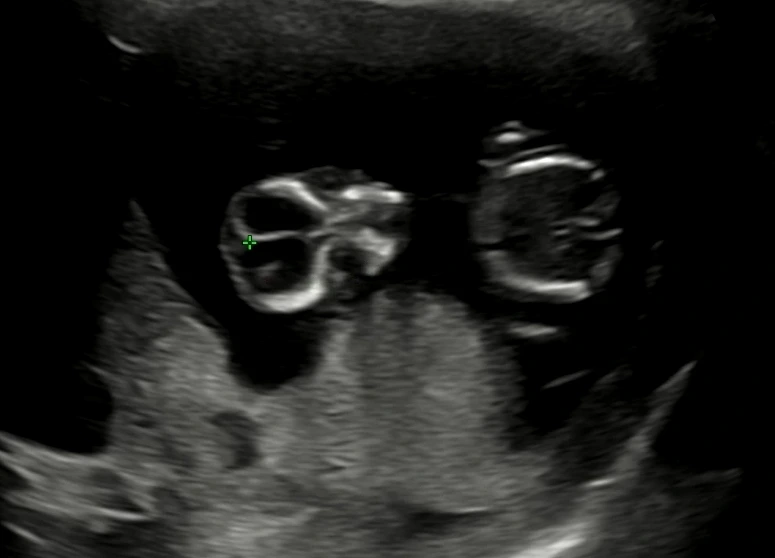

임신 9주차 초음파 (2023. 2. 11)

9주차에도 사이좋게 남편이랑 초음파를 보고 왔다! 초음파 속 사진이 뭐가 무엇인지 정확하게 잘은 모르지만 (ㅎㅎㅎ) 그저 신기해.

임신9주차 초음파